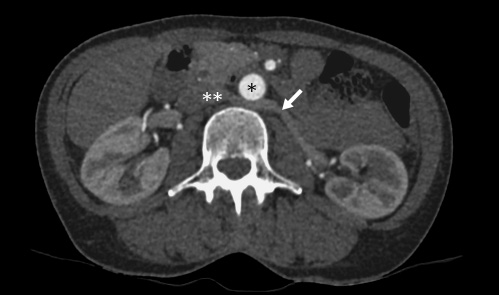

CT scan of a retroaortic left renal vein. *, aorta; **, vena cava; →, retroaortic left renal vein.

From 221 patients who underwent laparoscopic donor nephrectomy between 2011 and 2017, 11 (4.98%) showed the feature of a retroaortic left renal vein (Fig. 1). In 8 patients (72.7%) decision for left kidney donor nephrectomy was made.